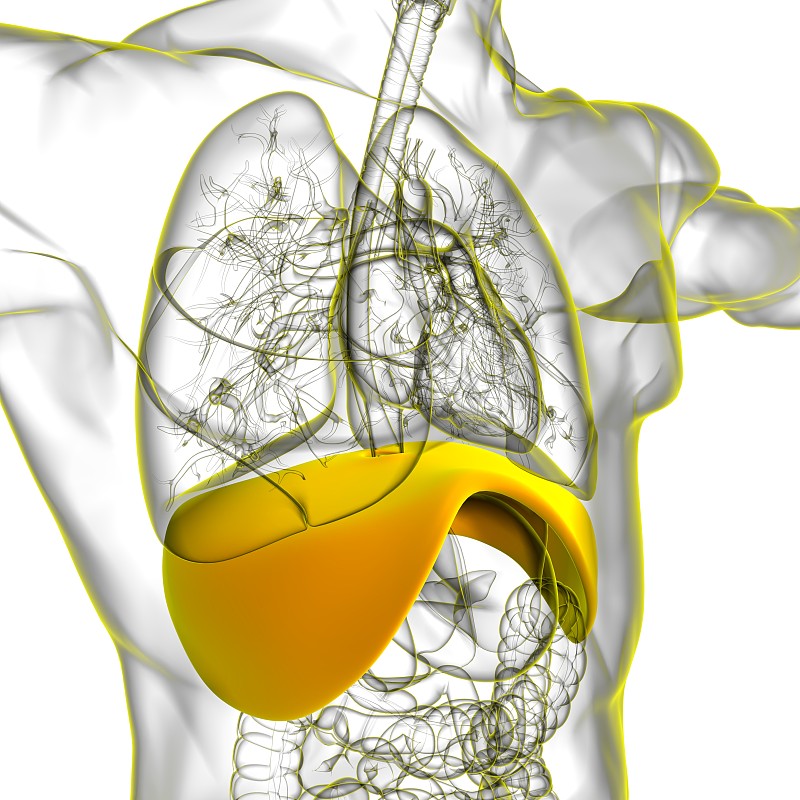

人类隔膜解剖学详情

JPG